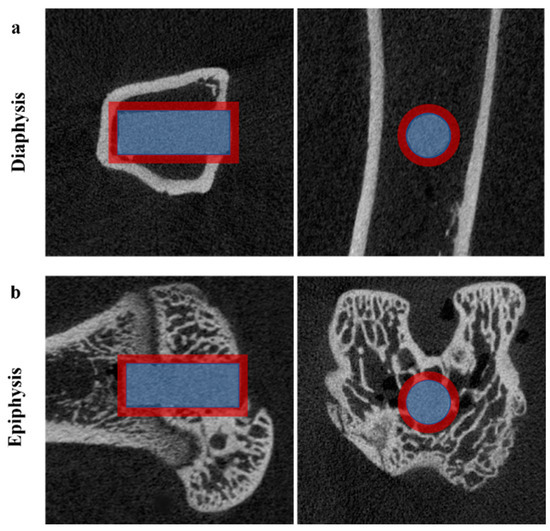

2.3. Micro-Computed Tomography Analysis

3.1. Micro-CT Evaluation